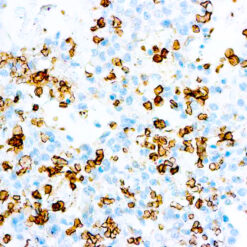

ERCC1

This antibody reacts with a 33-36 kDa protein known as ERCC1 (excision repair cross complementing) polypeptide. ERCC1 is required for nucleotide excision repair of damaged DNA and is homologous to RAD10. In mammalian cells, XPG cleaves 3’ of the DNA lesion while ERCC1-XPF complex makes the 5’ incision.

| Cellular Localization | Nuclear |

| Positive Control Tissue | Tonsil |